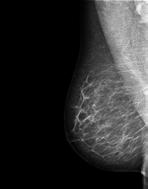

4 Prof. dr. Wiebren Tjalma, medisch coördinator van de borstkliniek

Geavanceerde beelden

wijzen de weg

‘Twee tumoren net op tijd ontdekt’

Geavanceerde medische beelden bren gen artsen dichter bij de juiste behandeling. In deze drie gevallen werd een ingrijpende operatie vermeden, een hersenprobleem doelgericht aan gepakt en een tweede tumor net op tijd ontdekt.

De medische beeld vorming is in volle evolutie. ‘We kunnen veel meer ziektebeel den tot in detail in beeld brengen’, zegt prof. dr. Paul Parizel, dienst hoofd radiologie. ‘Computerpro gramma’s maken het ook mogelijk om geavanceerde berekeningen te maken, bijvoorbeeld over de bloed toevoer naar bepaalde tumoren in de hersenen.’ De technieken hebben grote voordelen voor de behande ling: ‘Specialisten weten beter welk gebied ze moeten behandelen en kunnen voorspellen welke behande ling zal aanslaan.’

‘Voor een goede diagnose moet je samen met de radioloog alle infor matie in overweging nemen’, zegt prof. dr. Wiebren Tjalma, medisch coördinator van de borstkliniek. Hij geeft het voorbeeld van een vrouw van 55 die zelf een knobbeltje in haar borst ontdekte. Tjalma: ‘Tij dens het klinisch onderzoek voelde ik bij haar een letsel. Maar de beel den van de mammografie kwamen daar niet helemaal mee overeen: het letsel dat ik gevoeld had, leek me groter.’ Tjalma overlegde daarover met de radioloog: ‘Het was weefsel met erg veel klieren, waardoor we

De bijkomende beelden veranderden de hele aanpak.

eigenlijk niet goed konden zien of er eventueel nog een tweede letsel kon zijn. Daarom beslisten we om een bijkomende MRI en een echo te laten maken. Daarop zagen we inderdaad een tweede en een derde letsel in de borst.’

Na een biopsie in alle letsels bleek het om drie kwaadaardige gezwellen te gaan. Tjalma: ‘Dat ver anderde de hele aanpak. Eén gezwel konden we verwijderen met een borstsparende operatie, twee niet. Na overleg met artsen uit verschil lende disciplines was het advies om beide letsels te verwijderen, wat in de praktijk neerkwam op een borstverwijdering. Voor de patiënt was dat uiteraard een zware dobber, maar ook een geruststelling, omdat het tweede gezwel was ontdekt en behandeld. De multidiscipli naire aanpak voor de start van de behandeling was dus een groot voordeel voor de patiënte.’